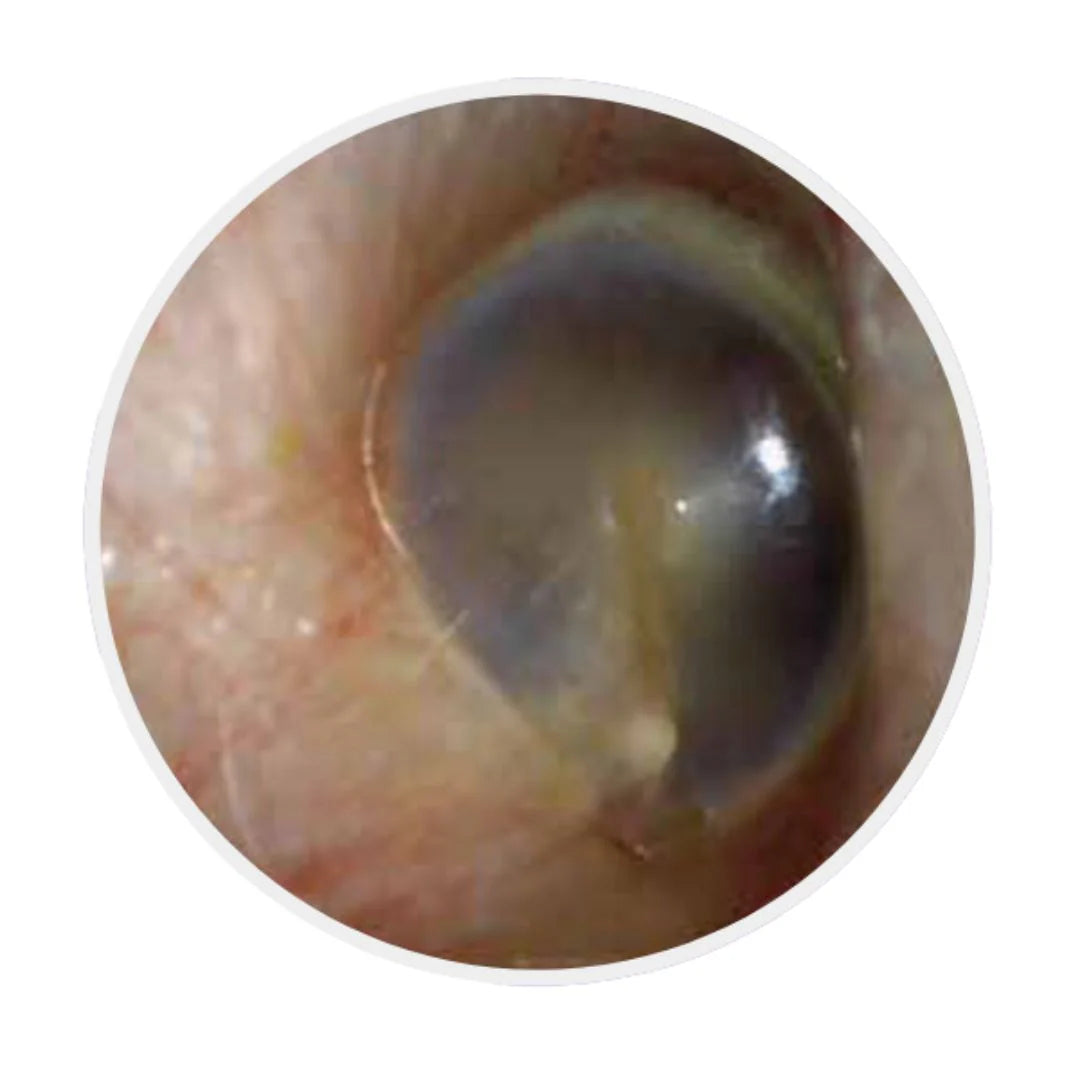

Après